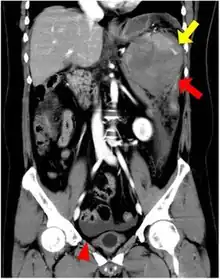

| CT scan of an accessory spleen (circular object in center of image) between the spleen and left kidney. | |

An accessory spleen is a small nodule of splenic tissue found apart from the main body of the spleen. Accessory spleens are found in approximately 10 percent of the population[1] and are typically around 1 centimetre in diameter. They may resemble a lymph node or a small spleen. They form either by the result of developmental anomalies or trauma.[2] They are medically significant in that they may result in interpretation errors in diagnostic imaging[2] or continued symptoms after therapeutic splenectomy.[1] Polysplenia is the presence of multiple accessory spleens rather than one normal spleen.

If splenectomy is performed for conditions in which blood cells are sequestered in the spleen, failure to remove accessory spleens may result in the failure of the condition to resolve.[1] During medical imaging, accessory spleens may be confused for enlarged lymph nodes or neoplastic growth in the tail of the pancreas,[5] gastrointestinal tract, adrenal glands or gonads.[2]